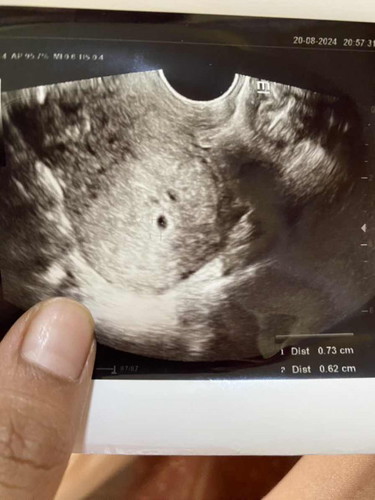

บ้านนี้แฝดคะ ถ้าได้แฝดคุณหมอจะแจ้งนะคะว่าได้แฝด

ถุงยังเล็กมากเลยแม่ รอลุ้นหมอนัดรอบหน้า

1ถุงต่อ1คนคะ ถ้าหมอไม่ได้แจ้งแฝดก็น่าจะ1คนคะ

ถ้าไม่ได้แจ้งว่าแฝดก็หน้าจะคนเดียวค่ะ